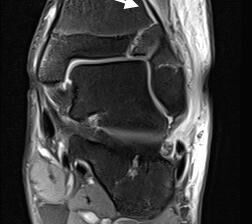

MRT

Die Kernspintomographie hat ihre Stärke in der Darstellung von Weichteilverletzungen. Insbesondere Verletzungen der Wachstumsfuge, des Periosts und der Bänder lassen sich gut visualisieren. Nachteilig ist die Untersuchungsdauer von 20-30 Minuten. Bleibt das Kind während dieser Zeit nicht ruhig liegen, kommt es zu Bewegungsartefakten, welche die Beurteilbarkeit der Bilder beeinträchtigen.

Os subfibulare

Multiple laminäre Ausrisse des fibularen Bandapparats aus der Fibulaspitze können zur Entwicklung eines Os subfibulare führen. Das Os subfibulare findet sich unterhalb der Fibulaspitze ventral der Peronealsehnen. Ohne Schmerzsymptomatik bzw. Aktivierung im MRT hat Das Os subfibulare keinen Krankheitswert. Ein mobiles Os subfibulare führt zu einer lokalen mechanischen Reizung teilweise in Verbindung mit einer Instabilität des Sprunggelenks. Im MRT zeigt sich eine Aktivierung des instabilen Areals. Bei anhaltenden Schmerzen besteht die Behandlung in einer operativen Entfernung des Knochens mit Refixation des Kapselbandapparats.

Fugengelenkfrakturen treten typischerweise vor dem 10. Lebensjahr auf, in einer Phase, in welcher die Wachstumsfugen noch weit offen sind. Dieser Frakturtyp betrifft fast ausschließlich den medialen Malleolus. Laterale Frakturen sind extrem selten, teilweise kommt es zu lateralen Bandverletzungen oder Fugenschaftfrakturen der distalen Fibula. Die Frakturlinie verläuft in einer Verlängerungslinie von der medialen Taluskante nach proximal. Häufig stellen sich Verletzungen des Innenknöchels im Röntgenbild schlechter dar, insbesondere wenn die Aufnahmen verdreht sind oder die Ebene der Fraktur bei geringer Dislokation verkippt zur Röntgenebene liegt. Besteht klinisch der geringste Hinweis auf eine Verletzung des Innenknöchels, muss aufgrund der Tragweite der Verletzung durch entsprechende Aufnahmen gegebenenfalls auch Schnittbildverfahren die Verletzung sicher diagnostiziert oder ausgeschlossen werden (Abb. 15).